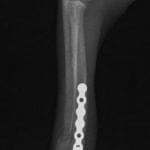

トイプードル 右遠位橈尺骨短斜骨折のALPSによる内固定

Locking Compression Plate

LCPは、スクリュー(ネジ)とプレート(金属の板)をロックする特殊な構造により骨折部位を固定する新しい世代のプレートシステムです。ひとつのホールでロッキングスクリューとスタンダードスクリューの使用を選択できるユニークな構造をしているため、骨折断端間の圧迫を目的とした従来型プレート固定法に加え、高い角度安定性を有するロッキングスクリューを用いた固定法の選択が可能です。従来のプレートシステムでは困難だった部分の骨折や癒合不全の症例に高い治療効果をもたらします。

当院ではAdvanced Locking plate system(ALPS)と、Locking compression plate system(LCPS)という骨接合法で骨折症例の治療を行っています。